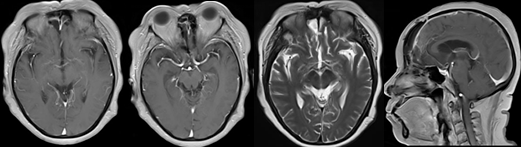

术后磁共振

6月后复查磁共振